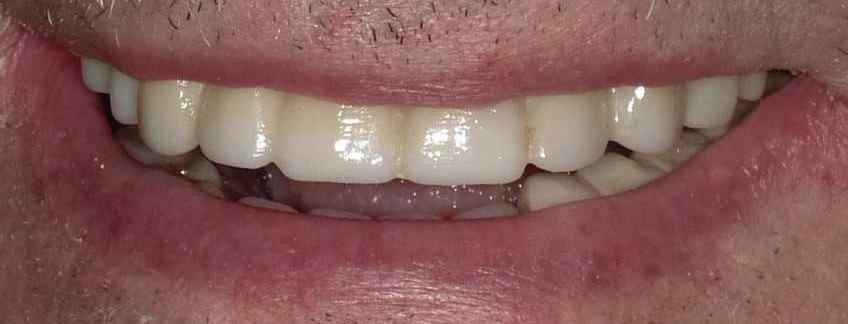

39 | Non-Extraction Orthodontic Treatment | Submitted By Let’s Smile Dental

Can just four implants replace all of the teeth on the top or the bottom of your mouth? Thanks to advances in dental implant technology, that answer is a resounding yes.

Believe it or not, tooth loss is extremely common among adults, especially as we age. In fact, more than 35 million people in America are missing all of their upper and/or lower teeth. Rather than living with the discomfort and hassles of dentures, many people are opting for what is called “all-onfour” dental implant restoration.

Here’s where it gets really interesting: You do not need a dental implant for each and every one of your missing teeth. All you need is four precisely placed implants on the top of your mouth, and four on the bottom, to restore your full smile. That’s the beauty of the all-on-four. And because the implant is made of titanium, it has the unique ability to fuse to living bone and function as part of it. So eventually, the dental implant becomes part of the jawbone and serves as a strong, long-lasting foundation for your new teeth.

Thanks to advances in dental implant technology, just four implants can replace all of the teeth on the top or the bottom of your mouth.

this bone fusion has another important benefit: it prevents future bone loss in the jaw. This helps to maintain a more youthful facial structure – and better oral health. But perhaps the biggest surprise about the all-on-four is how quickly it can transform your life.